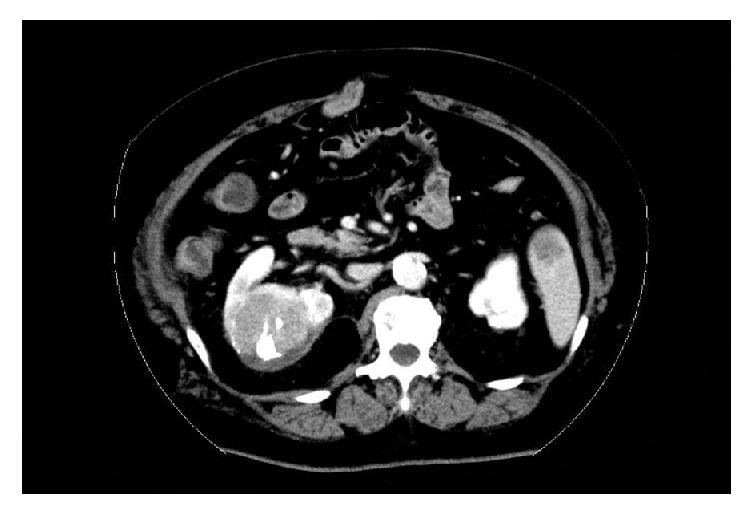

We report a rare life-threatening case of spontaneous rupture of renal metastasis from hepatocellular carcinoma (HCC) that was managed by emergent transcatheter arterial embolization (TAE). A 76-year-old woman diagnosed with HCC presented with acute back pain in her right side and was transferred to our hospital. Initial enhanced computed tomography revealed retroperitoneal hemorrhage from the right kidney, which was retrospectively diagnosed as a spontaneous rupture of the metastatic renal tumor from the primary HCC. Detailed examination identified an active retroperitoneal hemorrhage from the lesion and the patient's condition became hemodynamically unstable; hence emergent TAE was performed. The hospitalization period after the TAE was uneventful and sorafenib was subsequently administered. Unfortunately, two months after the TAE, the tumor locally progressed within the retroperitoneal space. Tumors were controlled by repeated TAE as the patient did not want to undergo a nephrectomy. Consequently, she survived for more than one year after emergent TAE, exhibiting low levels of tumor marker. After rupture of the metastatic renal HCC, tumors were expected to progress into the retroperitoneal space, and nephrectomy was the next possible radical treatment to offer the best chance of long-term disease control.

我们报告了一例罕见的、危及生命的肝细胞癌(HCC)肾转移灶自发性破裂病例,该病例通过紧急经导管动脉栓塞术(TAE)进行治疗。一名76岁被诊断为HCC的女性因右侧急性背痛就诊,并被转至我院。初次增强计算机断层扫描显示右肾腹膜后出血,经回顾性诊断为原发性HCC肾转移瘤自发性破裂。详细检查发现病灶处有活动性腹膜后出血,患者血流动力学不稳定;因此进行了紧急TAE。TAE术后住院期间情况平稳,随后给予索拉非尼治疗。不幸的是,TAE术后两个月,肿瘤在腹膜后间隙局部进展。由于患者不愿接受肾切除术,通过重复TAE控制了肿瘤。结果,她在紧急TAE术后存活了一年多,肿瘤标志物水平较低。肾转移性HCC破裂后,肿瘤预计会向腹膜后间隙进展,肾切除术是下一个可能的根治性治疗方法,有望提供最佳的长期疾病控制机会。